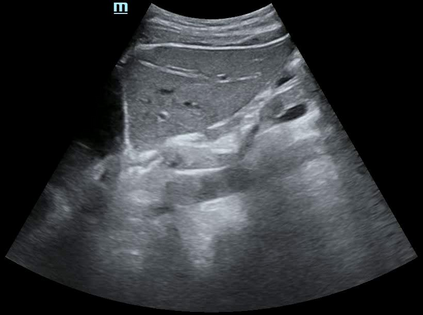

Most deep neural networks (DNNs) based ultrasound (US) medical image analysis models use pretrained backbones (e.g., ImageNet) for better model generalization. However, the domain gap between natural and medical images causes an inevitable performance bottleneck. To alleviate this problem, an US dataset named US-4 is constructed for direct pretraining on the same domain. It contains over 23,000 images from four US video sub-datasets. To learn robust features from US-4, we propose an US semi-supervised contrastive learning method, named USCL, for pretraining. In order to avoid high similarities between negative pairs as well as mine abundant visual features from limited US videos, USCL adopts a sample pair generation method to enrich the feature involved in a single step of contrastive optimization. Extensive experiments on several downstream tasks show the superiority of USCL pretraining against ImageNet pretraining and other state-of-the-art (SOTA) pretraining approaches. In particular, USCL pretrained backbone achieves fine-tuning accuracy of over 94% on POCUS dataset, which is 10% higher than 84% of the ImageNet pretrained model. The source codes of this work are available at https://github.com/983632847/USCL.